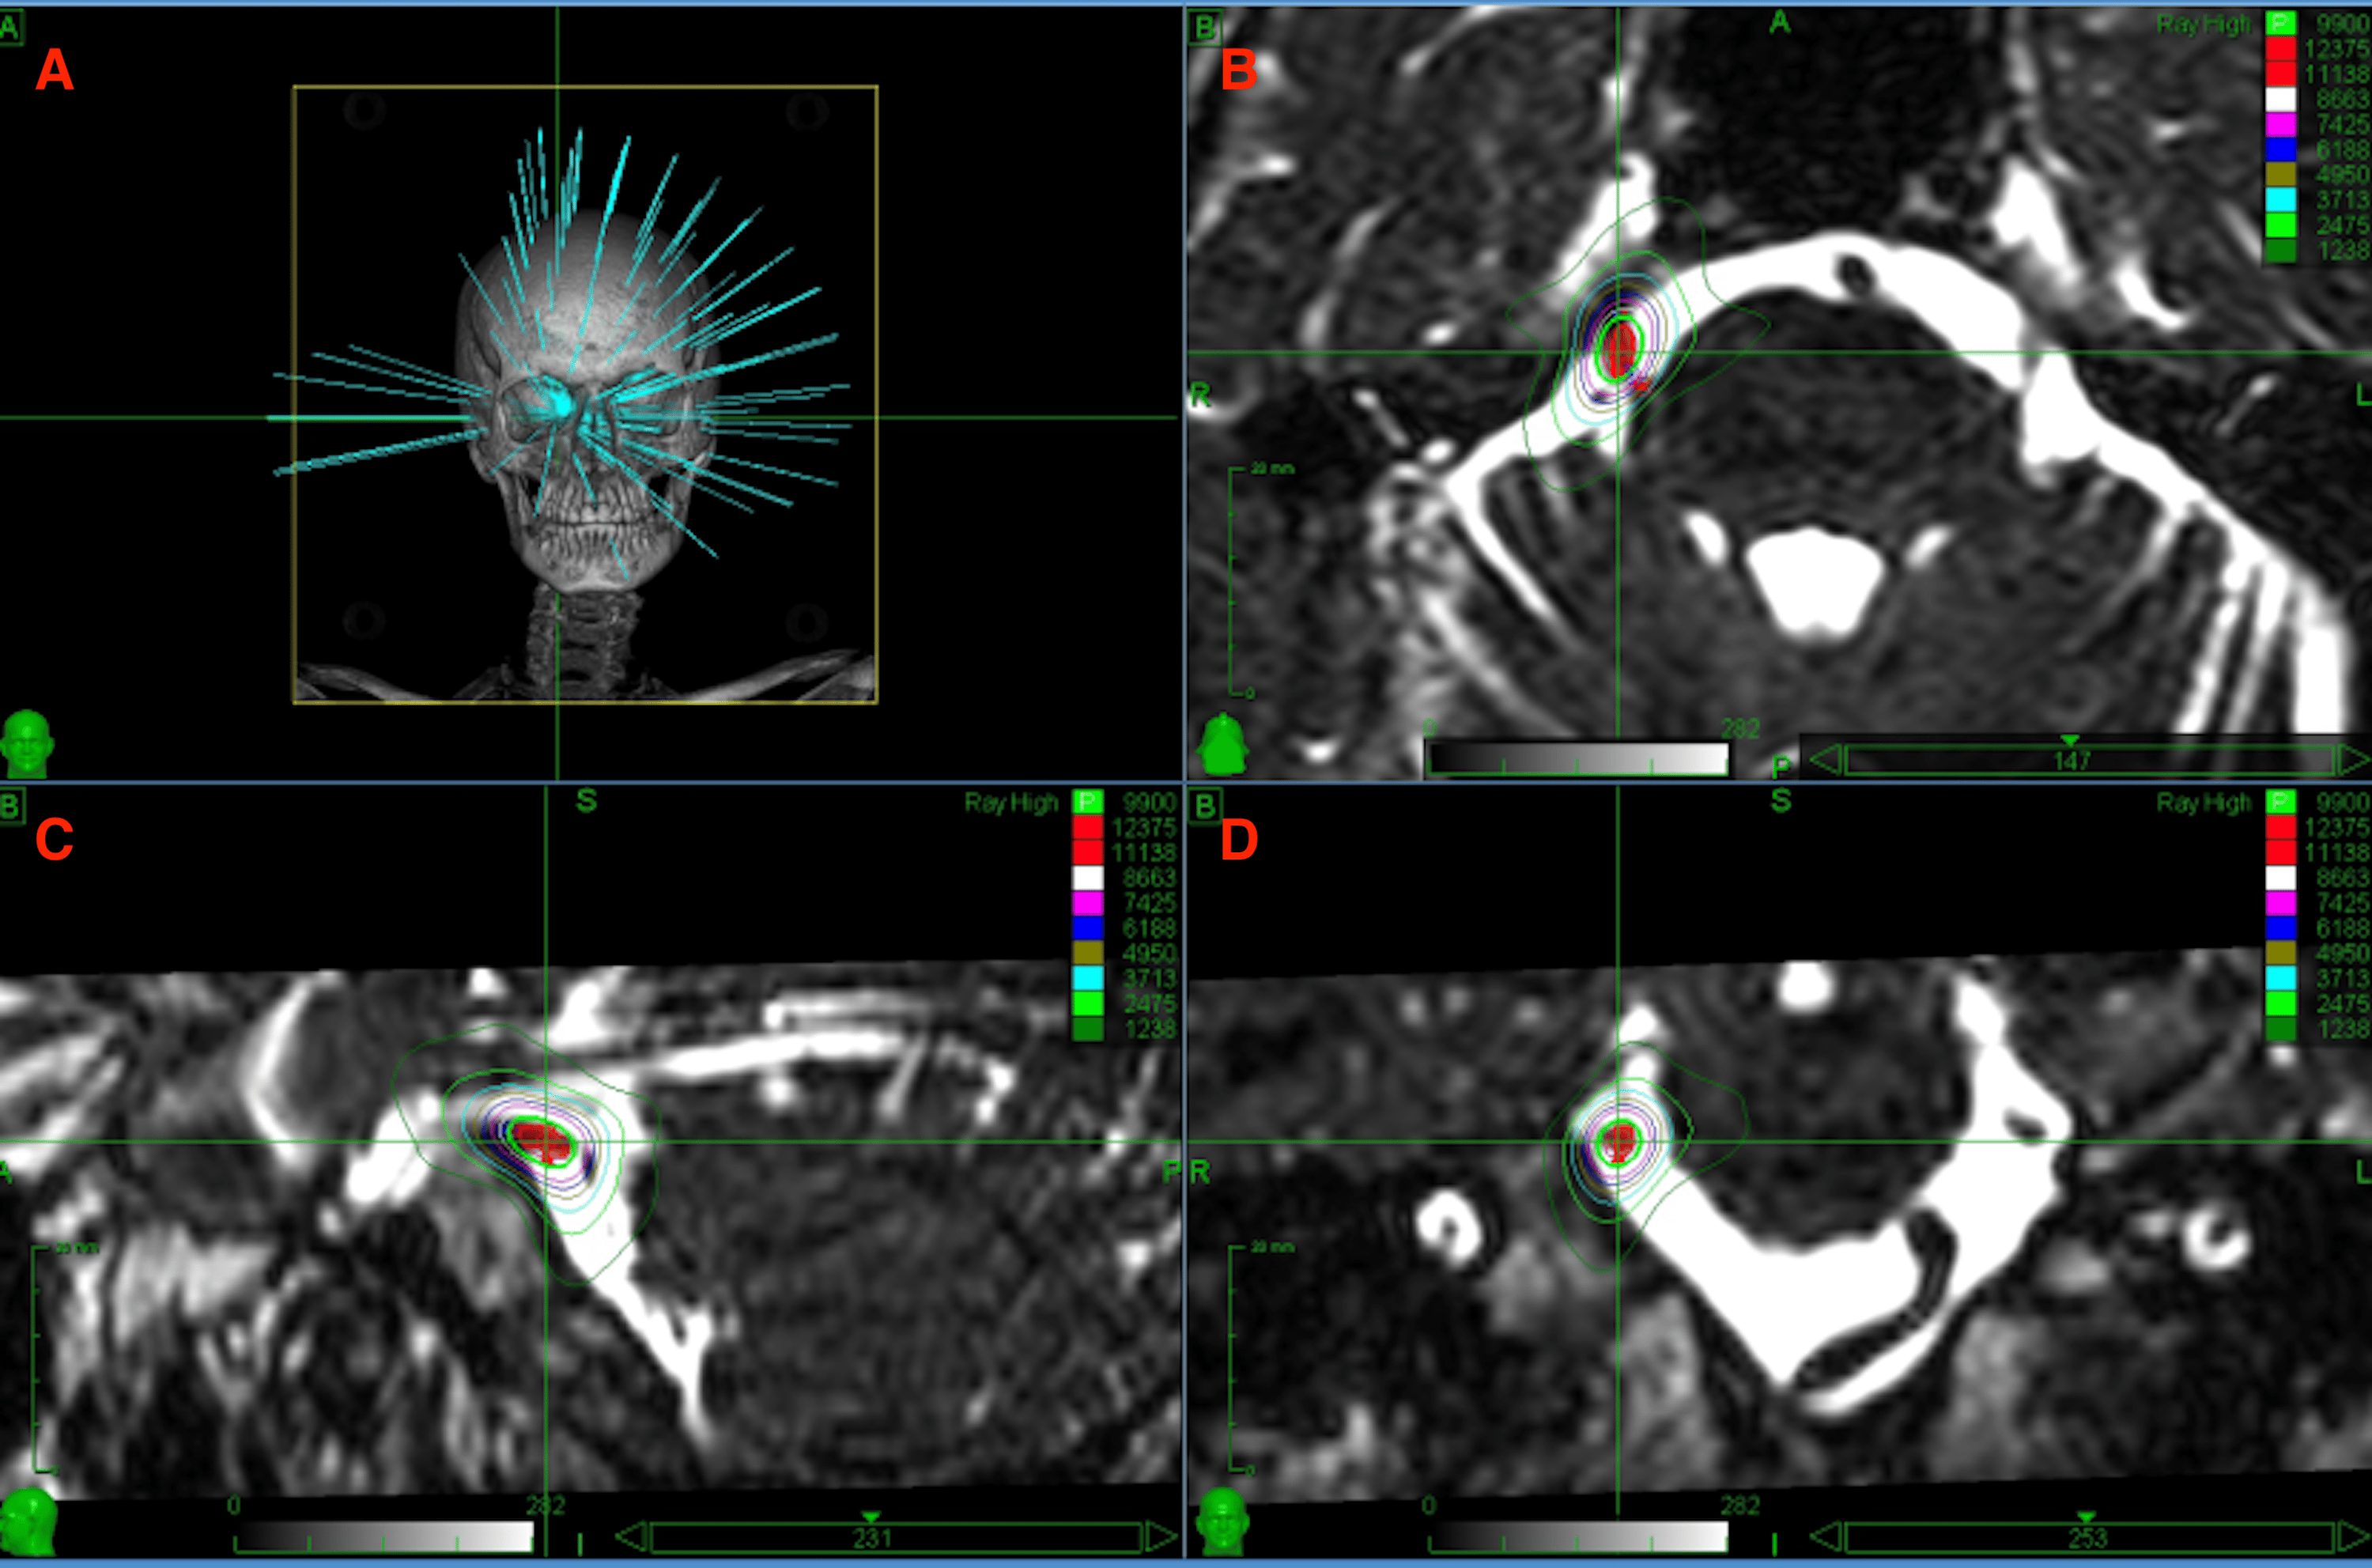

Figure 1 from Radiosurgery for trigeminal neuralgia using a linear accelerator with BrainLab

Figure 1 from Radiosurgery for trigeminal neuralgia using a linear accelerator with BrainLab Radiosurgery Trigeminal Neuralgia if you appear to have trigeminal neuralgia, the exam can help uncover which branches of the trigeminal. trigeminal neuralgia is a chronic pain disorder of one or both of the trigeminal nerves, which relay sensory information between your brain and. The aims of this systematic review are to provide an objective summary of the published. stereotactic surgery. Radiosurgery Trigeminal Neuralgia.